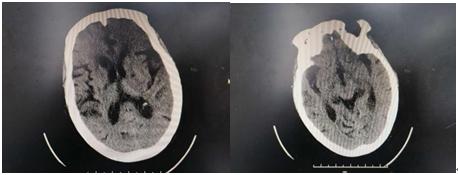

头颅及胸部CT:

1. 双侧基底节区及侧脑室旁多发腔梗灶,脑白质脱髓鞘;